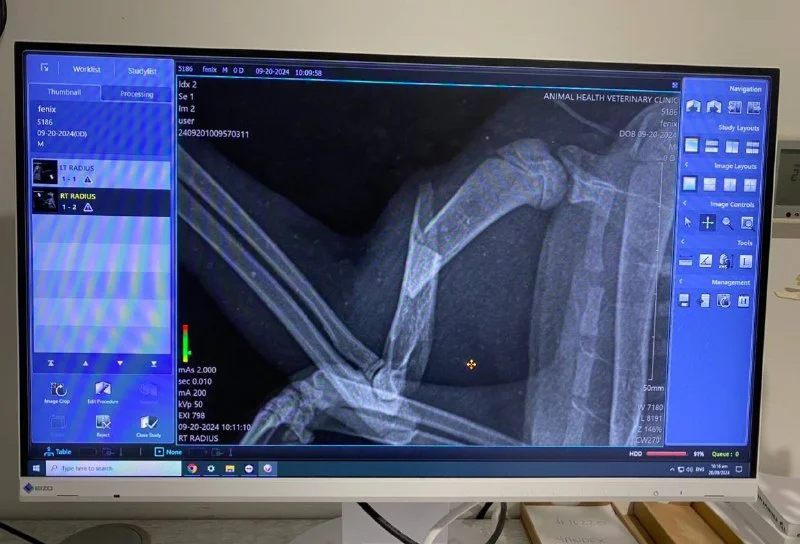

Здравствуйте! Срочно ищем семью или передержку хотя бы на две недели… нашла Зайку в кустах с перебитой лапой. Благодаря отзывчивым людям из чата животных Кипра - была собрана вся необходимая сумма на операцию. Зайку прооперировали в пятницу и оставили до понедельника в стационаре. Дальше нам идти некуда … 💔 ей нужно ограничить движение, давать 10 дней антибиотики и болеутоляющие, и вынуть спицу через 14 дней…

Пожалуйста, помогите найти или передержку этому бедному запуганному ребенку.

Она очень нежная, ласковая, все время мурлычет. Очень добрая! Пожалуйста, помогите!